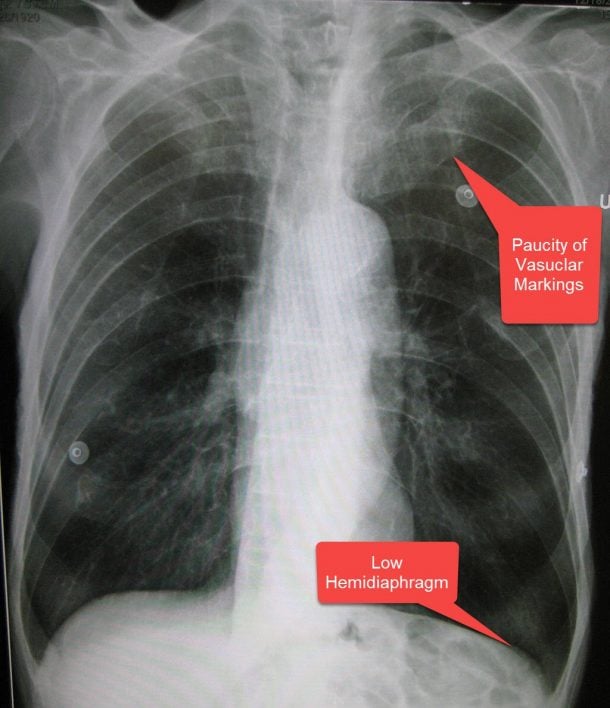

Posterioranterior chest Xray revealing hyperinflation, flattened What Does A Flattened Diaphragm Mean This movement creates a vacuum in. If you have hyperinflated lungs, this means that they’re holding too much air. When you breathe in, your diaphragm contracts (tightens) and flattens, moving down towards your abdomen. Medical imaging scans of the lungs in a person with copd may show visible air pockets, a lowered or flattened diaphragm, and lung enlargement. Diaphragm paralysis. What Does A Flattened Diaphragm Mean.

What Does A Flattened Diaphragm Mean . This can contribute to shortness of breath (dyspnea), which is the primary symptom of copd. Diaphragm paralysis is the loss of control of one or both sides of the diaphragm. This movement creates a vacuum in. When you breathe in, your diaphragm contracts (tightens) and flattens, moving down towards your abdomen. Medical imaging scans of the lungs in a person with copd may show visible air pockets, a lowered or flattened diaphragm, and lung enlargement. “a paralyzed diaphragm occurs when there is phrenic nerve damage or. If you have hyperinflated lungs, this means that they’re holding too much air. When you take a breath, the diaphragm contracts and flattens, which causes your chest cavity to expand. Chronic obstructive pulmonary disease (copd) often leads to hyperinflated lungs. The heart may also appear.

The heart may also appear. “a paralyzed diaphragm occurs when there is phrenic nerve damage or. Diaphragm paralysis is the loss of control of one or both sides of the diaphragm. When you take a breath, the diaphragm contracts and flattens, which causes your chest cavity to expand. If you have hyperinflated lungs, this means that they’re holding too much air. When you breathe in, your diaphragm contracts (tightens) and flattens, moving down towards your abdomen. Chronic obstructive pulmonary disease (copd) often leads to hyperinflated lungs. This movement creates a vacuum in. This can contribute to shortness of breath (dyspnea), which is the primary symptom of copd. Medical imaging scans of the lungs in a person with copd may show visible air pockets, a lowered or flattened diaphragm, and lung enlargement.